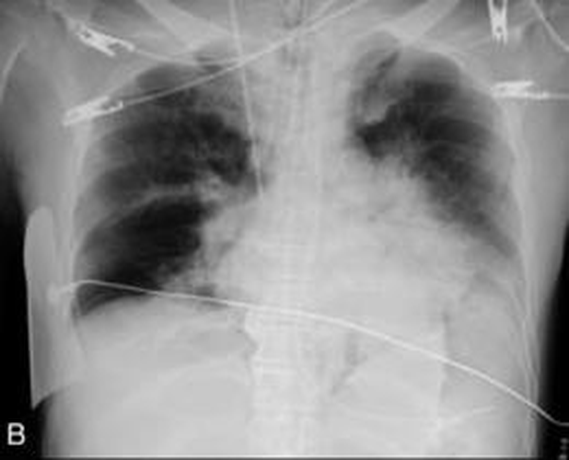

Challenging Examples from Self-Evolving Trained Vision-Language Model [Uncaptioned image] [Uncaptioned image] Question (Iter 1) Approximately how many lung fields are visible in the X-ray image? Which skeletal structure most likely belongs to a bird with hollow bones? Question (Iter 2) On a thoracic x-ray, the right lobe of the lung is more spread out compared to the left lobe. If the right lobe is given a score of 1 and the left lobe is given a score of 0, what is the difference in scores between the right and left lung lobes? On which figure does the long neck of the dinosaur have the greatest horizontal angle with the vertical axis? Question (Iter 3) On which rib is the line approximately 2.5 cm above the image’s midpoint? Which skeletal structure is most likely to have evolved secondary to flying abilities and which is less likely to have this trait?

Table 4 presents example questions generated by the self-evolving Vision-Language Models across three training iterations. Iteration 1 questions focus on direct observation, such as counting or identifying objects. Iteration 2 introduces relational and comparative reasoning, requiring the model to assess differences or evaluate spatial angles. Iteration 3 further increases complexity with multi-step reasoning and inference, including precise localization and causal relationships. This progression demonstrates a systematic increase in question difficulty, providing increasingly challenging training signals that encourage the model to adapt and improve its reasoning capabilities. Such a design ensures that both the Questioner and Reasoner co-evolve, progressively enhancing the overall performance of the system.